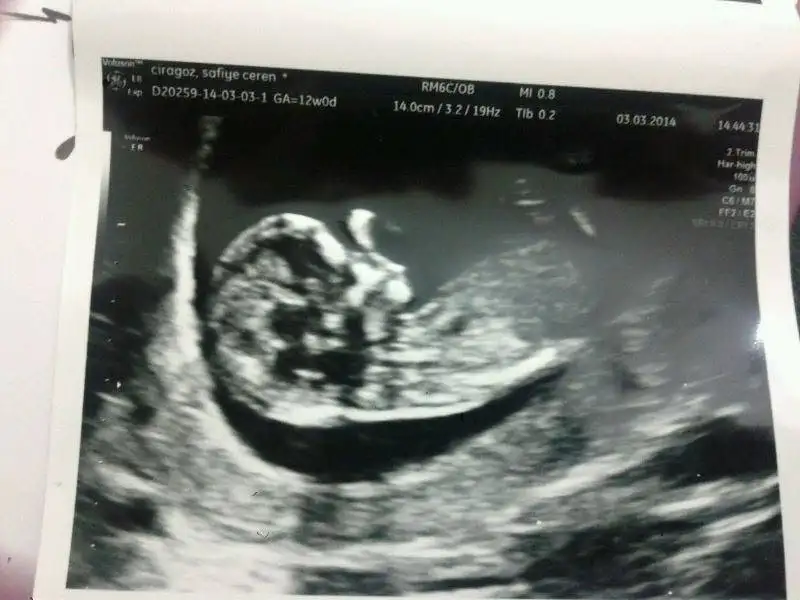

Bebegim 12+6 gunluk burada. Doktor cinsiyeti icin erken dedi. Elimizdeki tek resim bu.

Yorumlarinizi esirgemeyin.

Selam tekrar. Bebegin icin defne kiz demisti en son. Bugun erkek oldugunu ögrendik. Tesekkurler yorum yapan herkese.

Bir de bebegin basi fazla asagidaydi normal dedi hemsire ama ben tedirgin oldum. Acaba sizde de oldu mu böyle bir sey?